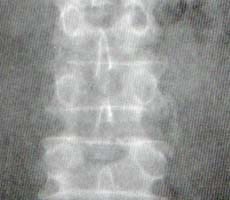

Sindesmofito no marginal: en este caso la calcificación se origina en la porción media del cuerpo vertebral extendiéndose hasta la región equivalente del cuerpo adyacente dejando una zona radiolúcida entre los cuerpos y la calcificación. Este tipo de calcificación puede comprometer más de dos niveles de la columna (Figura 2).

Figura 2. Sindesmofito no marginal en un paciente con Síndrome de Reiter.

Obsérvese que sale de la mitad del cuerpo vertebral superior y llega al adyacente,

por debajo de la esquina del mismo.